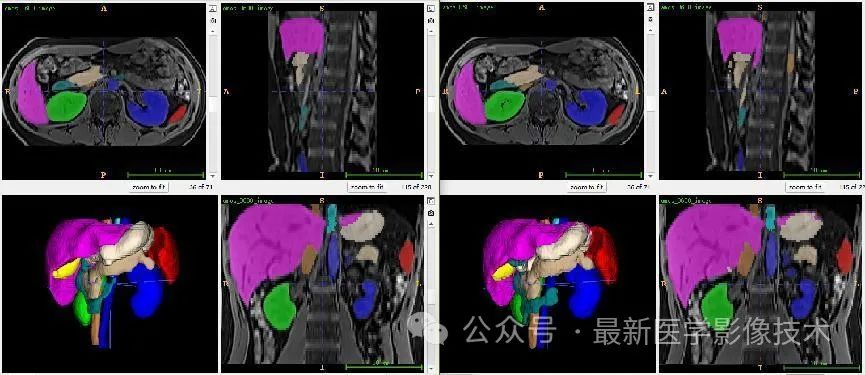

12、验证集分割结果

左图是金标准结果,右图是预测结果。